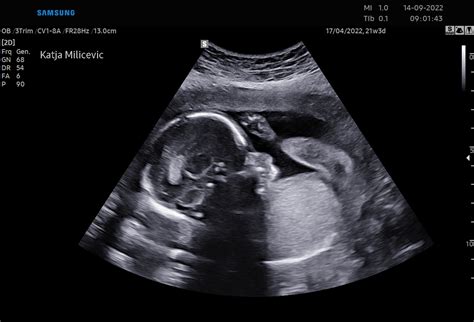

Čeprav v tem tednu običajno ni posebnega ultrazvočnega pregleda, se mnoge bodoče mamice v tem času zanimajo za amniocentezo, invaziven poseg za odkrivanje genetskih motenj. Preden se odločite za ta postopek, se dobro posvetujte s svojim ginekologom, saj obstajajo tudi druge metode pregleda, kot je morfologija, ki sledi okoli 20. tedna.